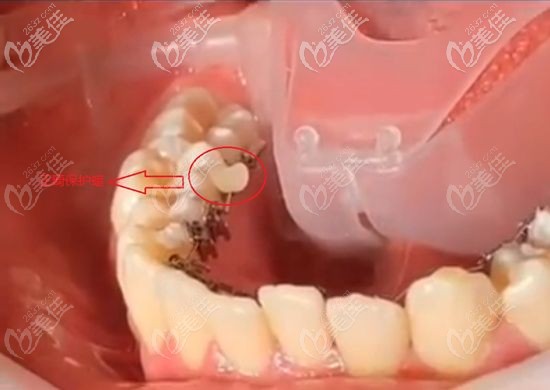

鄭州金水春芽口腔門診部

人氣 0.2 活躍 6.8 診療科目 口腔科 //醫(yī)學影像科 | X線診斷專業(yè)(限口腔)******